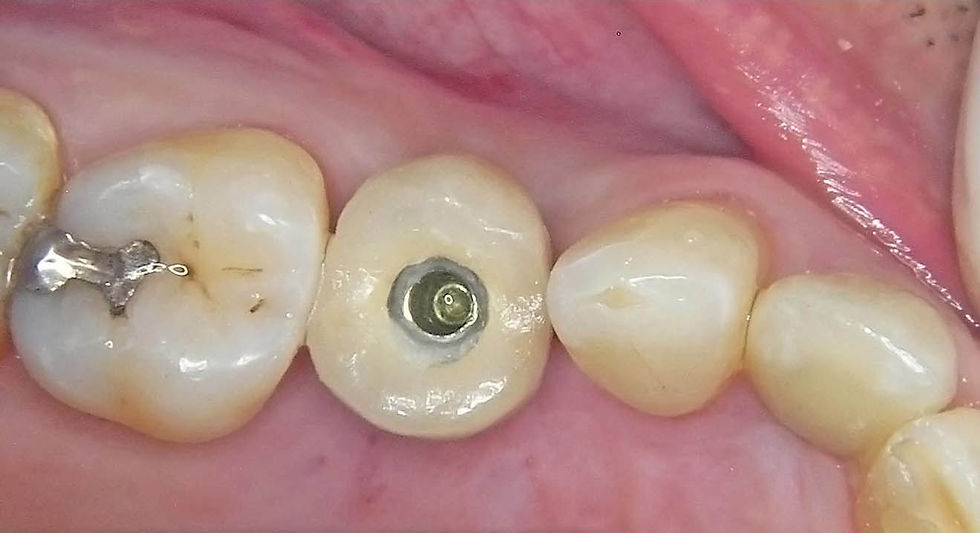

Surgical phases for the delayed flapless insertion of a Prama RF 4.25x13 mm implant with adequate primary stability to proceed with an immediate temporarization.

Positioning of a post with retentive notches and occlusal perforation of the old metal-ceramic crown to access to the prosthetic screw.

The temporary crown, finished and polished, is tightened in place, radiographic checking the correct fit and the adequate emergence profile.

Intraoral aspect of the temporary crown fastened after 50 days from the surgery.